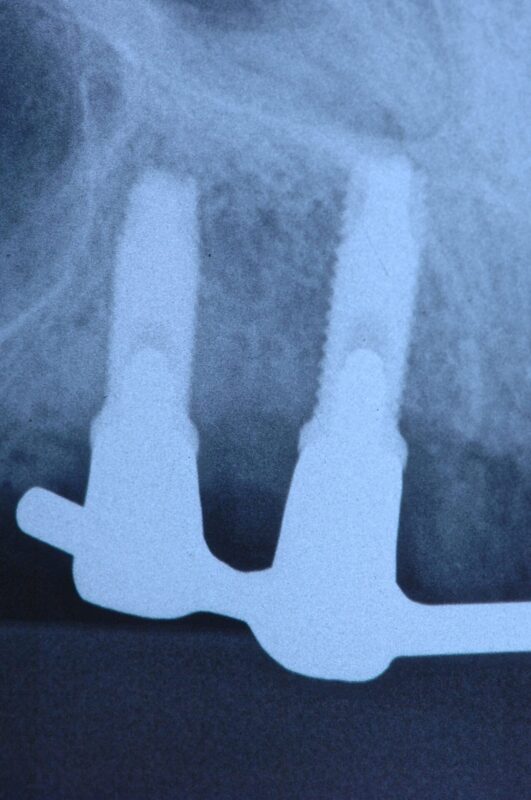

ドルダーバー

ご高齢の方ですが、20年以上前に処置しました。

念の為装着後初めて(20年以上経過)いったん除去したところ(単にネジ止めされているだけですぐ

外れます)2カ所に炎症がありました。

本体には全く問題ありません。

金合金で作製しているため、組織親和性は高いです。

もちろん、インプラント本体にも全く問題ありません。

使用インプラントは3i(アメリカ)。

原因はスクリューが破折していましたので、念の為4本とも全て新しいものと交換しました。